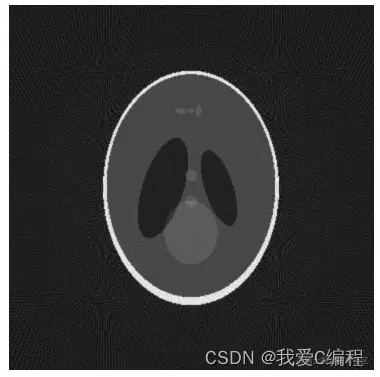

在研究从投影重建图像的算法时,为了比较客观的评价各种重建算法的有效性,人们常选用公认的Sheep-Logan 头模型作为研究对象。该模型由10个位置、大小、方向、密度各异的椭圆组成,象征一个脑断层图像。

2.仿真效果预览

matlab2022a仿真结果如下:

I=phantom(256);  %生产头部模型图

imshow(I);       %显示图像